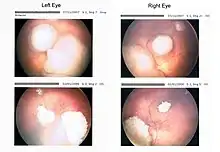

Drawing of a large retinoblastoma

Drawing of a large retinoblastoma Aspect of trilateral retinoblastoma on MRI

Funduscopic finding of a retinoblastoma Ocular fundus aspect of retinoblastoma

Ocular fundus aspect of retinoblastoma Large exophytic white tumor with foci of calcification producing total exudative retinal detachment